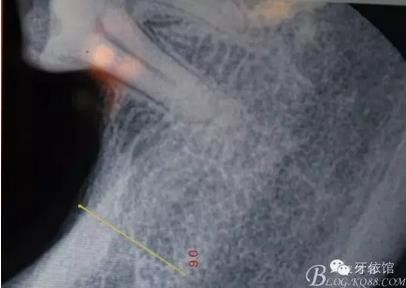

患者女,45歲,右上6于多年前牙髓失活后充填,未作冠,術(shù)前不久,進食時不幸劈裂。檢查發(fā)現(xiàn):右上6充填物脫落,近遠中向縱劈,x光見根管內(nèi)無充填物。同時有右上7、右下7缺失。計劃:右上6,7,右下7種植修復(fù)。右上6為即可種植,同時做內(nèi)提。

X光片